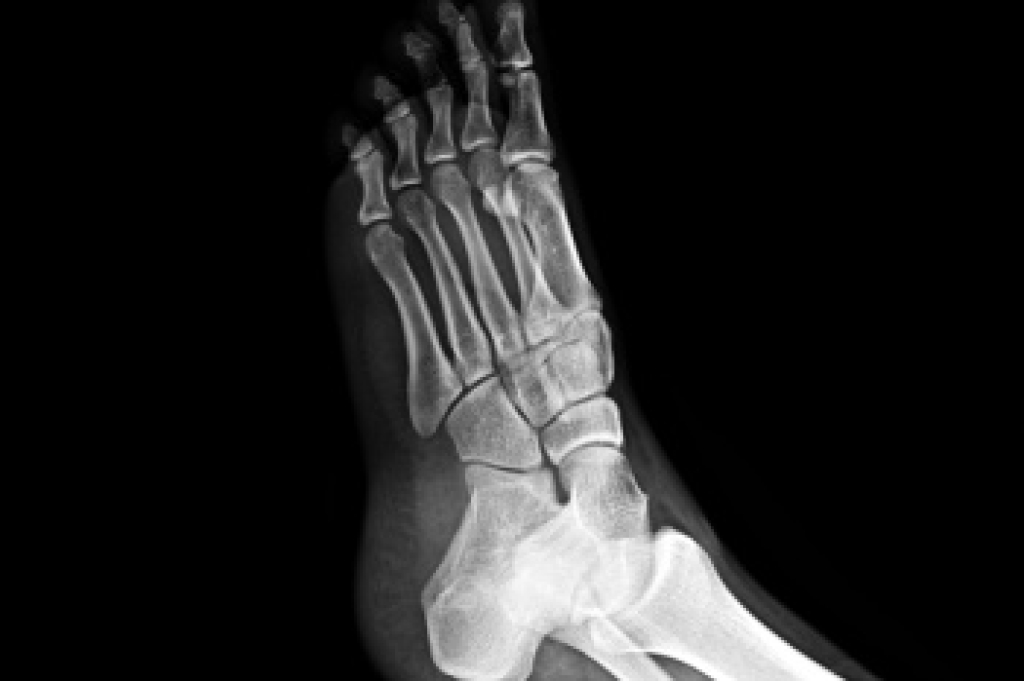

To figure out the cause of foot pain, podiatrists utilize several different methods. This can range from simple visual inspections and sensation tests to X-rays and MRI scans. Prior medical history, family medical history, and any recent physical traumatic events will all be taken into consideration for a proper diagnosis.

A metatarsal stress fracture is a tiny crack in one of the long bones of the foot, often caused by repetitive stress or overuse during activities like running or jumping. Symptoms include localized pain, swelling, and tenderness that worsens with activity. Preventing metatarsal stress fractures involves gradually increasing activity levels, wearing supportive footwear, and incorporating rest days into your exercise routine. Proper warm-up and stretching before activities can also reduce the risk. Treatment typically includes rest, icing the affected area, and using orthotics or supportive footwear to relieve pressure on the foot. In severe cases, immobilization with a cast or walking boot may be necessary. A podiatrist can conduct a thorough evaluation, possibly using imaging studies, and recommend appropriate treatments to promote healing and prevent further injury. Early intervention can speed up recovery and prevent long-term complications. If you suspect a metatarsal stress fracture or experience persistent foot pain, it is suggested that you make an appointment with a podiatrist.